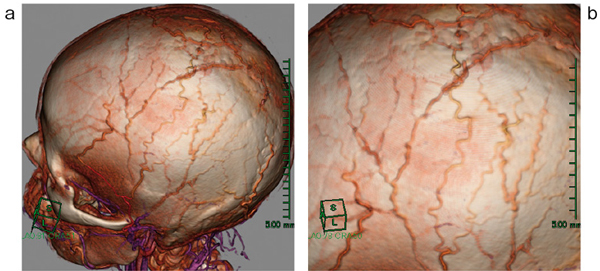

術後のフォローアップとして,同症例を同様に撮影した画像を提示する。右の浅側頭動脈,静脈が結札されnidusが切除されている(図3)。また,対側から頭頂部にかけての末梢血管を描出するために,骨のマスクを膨張させ,オパシティを調整することで頭頂部の末梢動脈も確認できた(図4)。

図4 症例1:頭頂部の末梢血管像

a:頭頂部の末梢血管の全体像 b:拡大像